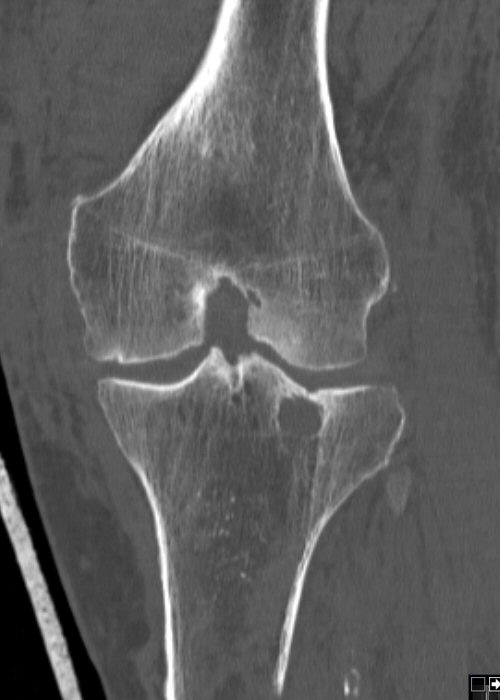

Till vänster exempel på odislocerad fraktur i laterala tibiakondylen, behandlad icke-kirurgiskt. Högra bilden efter 2 år, börjat utveckla artros.